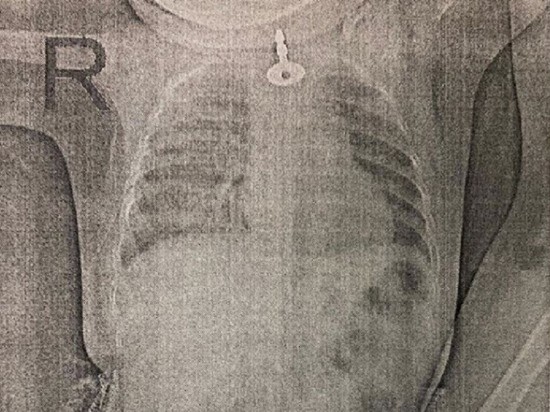

На рентгеновском снимке ребенка врачи увидели, что проглоченный ключ застрял в верхнем сужении пищевода. Малышке требовалась сложная операция.